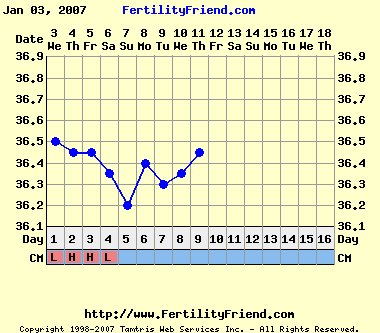

Na, ma ismét kicsit jobb hangulatban vagyok, bár baromi álmos vagyok. Viszont közeleg a pé-em, és ez felvillanyoz. Tegnap megcsináltam az első LH tesztet, de még alig látható a második vonal, szerintem akkor még odébb van. Remélem is, mert még eddig nem sikerült elkapnom a férjem. Szombaton meg utazunk apukámékhoz, ott sem igazán lesz rá alkalom, talán vasárnap este. Azért holnapra már tervezem...

És tényleg, miért is mondod, hogy olyan rémes ez a görbe?! A mostani leesés miatt? Merthogy nekem még eddig egy ciklusban sem rajzolt a fertility ilyen határozott pé-es piros vonalat. Én mindig csak szaggatottat kapok.

Mo, hát, a görbéd valóban érdekes, reméljük, hogy semmiféleképpen nem a mensit mutatja a hőd leesése.

Hát, ez a görbe, ha már később volna néhány nappal, felérne egy pé-el! Remélem, még nem volna. Azért az kicsit korai lett volna. Meg az LH teszt sem jelezte. Bár a PG53 mutatott ezt-azt. Na, ezt a gondolatot gyorsan el is hesegetem magam elől!